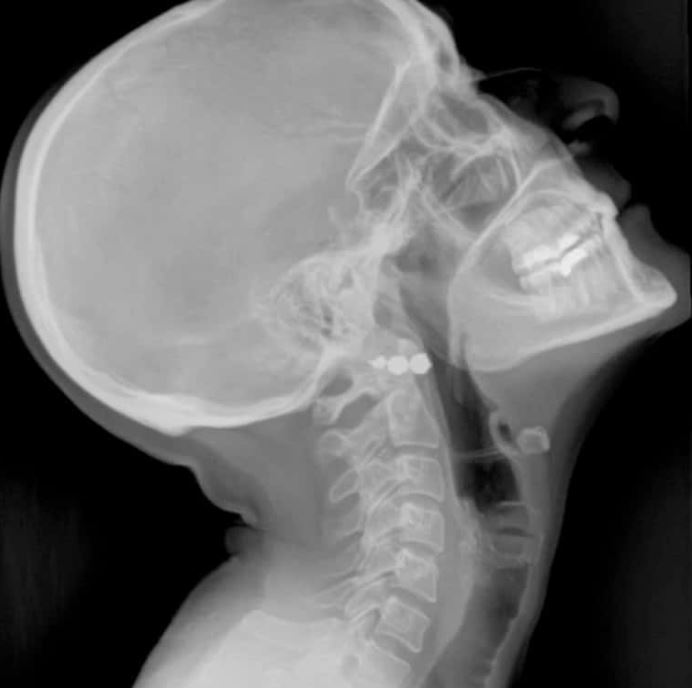

डिजिटल रेडिओग्राफी

डिजिटल रेडिओग्राफी हे वैद्यकीय इमेजिंग तंत्र आहे जे क्ष-किरण प्रतिमा कॅप्चर करण्यासाठी डिजिटल सेन्सर वापरते, कार्यक्षम प्रतिमा प्रक्रिया, कमी रेडिएशन एक्सपोजर आणि निदानासाठी तत्काळ प्रतिमा उपलब्ध करून देते.